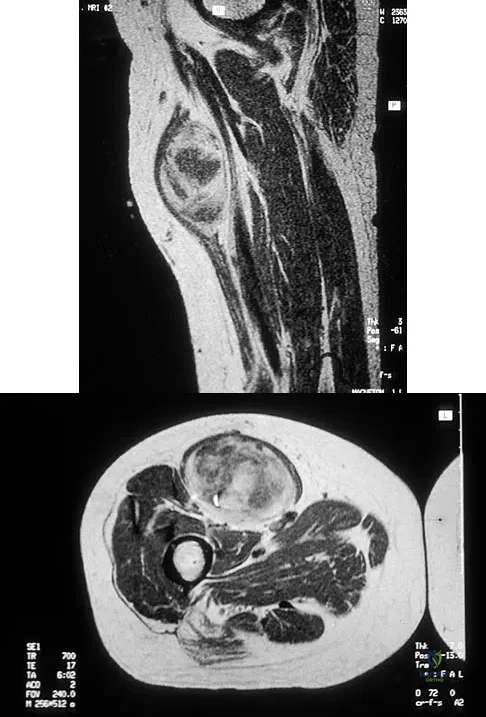

A 20-year-old man sustained an injury to his arm during a tug-of-war contest. An MRI scan is shown in Figure 18. What is the most likely diagnosis?

The MRI scan reveals a transection of the biceps muscle. The underlying brachialis is intact. This injury can occur as a result of a cord wrapped around the upper arm. Care should be taken to ensure that there is no concurrent vascular injury. A posterior subcutaneous lipoma appears as a well-encapsulated mass on T2-weighted images. Heckman JD, Levine MI: Traumatic closed transection of the biceps brachii in the military parachutist. J Bone Joint Surg Am 1978;60:369-372.